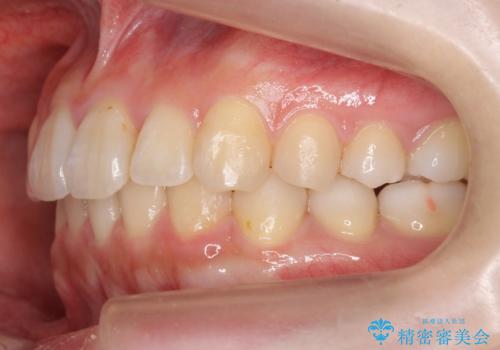

軽度の前歯のがたつき 下の前歯が生まれつき少ない

- 前歯のがたつきを主訴に来院。

下の前歯が生まれつき3本でした。

そのため、上の前歯が少し余るような形で出っ歯になっていたため、スペースを作って引っ込めています。

下を3本でそのまま並べてあるため、上下の正中は合いません。

合わせようとすると抜歯か、下の隙間を無理やり開けてブリッジとなりますが、そこまでするメリットがないため、下はそのままの歯の数を生かしています。